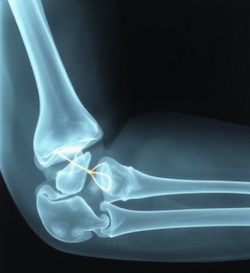

A radiograph (x-ray) of a broken boneThe statute treats “broken bones” as a self-defining concept. It does not qualify the term in any way. There is no requirement that the fracture be severe, require surgery, or even require treatment. The statute simply says: broken bones.

Thus, if the victim falls to the ground while protecting their dog from an attack, the victim’s mere hairline fracture to the hip, elbow, knee, or wrist will suffice.